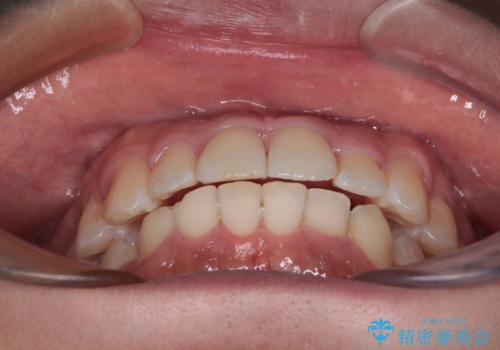

前方に捻れた前歯を治したい インビザライン矯正治療

- 前歯のデコボコを治したいとのことで来院された患者様です。

上下顎ともに歯列全体の後方移動とIPR(歯と歯の間を削る)によってデコボコが解消するように設計し、インビザラインにより治療を行うこととしました。